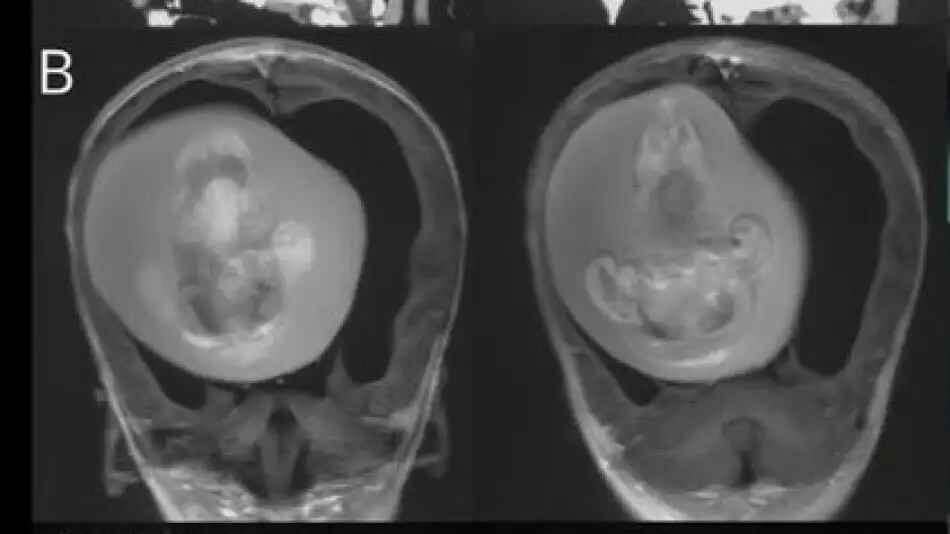

Un hecho poco común y sorprendente tuvo lugar en China, donde médicos lograron extraer un feto de la cabeza de una niña de un año de edad. El caso se conoce como “Fetus-in-fetu” o “gemelo parásito” y solo se ha documentado en 18 casos en todo el mundo dentro del cráneo.

Los padres de la menor notaron que tenía la cabeza agrandada y problemas motores, por lo que acudieron a los especialistas, quienes descubrieron la presencia del feto en la cabeza de la niña.

El feto extraído, que medía alrededor de cuatro pulgadas de largo, había desarrollado extremidades superiores, huesos e incluso uñas, lo que demostró que había continuado su crecimiento en la cabeza de la niña durante meses. Los médicos explicaron que el feto estaba presionando contra el cerebro de la niña, lo que le causaba esos problemas.

Según los especialistas, el feto logró sobrevivir tanto tiempo porque ambos compartían el suministro de sangre. El caso fue publicado en la revista Neurology de la Academia Estadounidense de Neurología. Actualmente, se desconoce si la niña tendrá secuelas a futuro.

Este tipo de caso es poco común y ocurre cuando los gemelos se fusionan en el útero y uno se desarrolla físicamente dentro del otro.